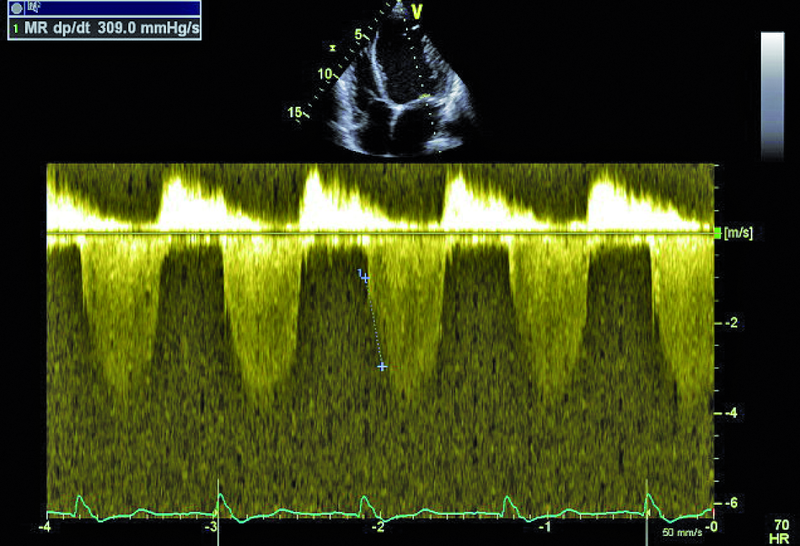

Kobieta, lat 41. Jakie patologie można rozpoznać na zamieszczonych rycinach?

3. Niedomykalność zastawki mitralnej (ryc. 3).

4. Ciężka dysfunkcja skurczowa lewej komory (ryc. 3-5).